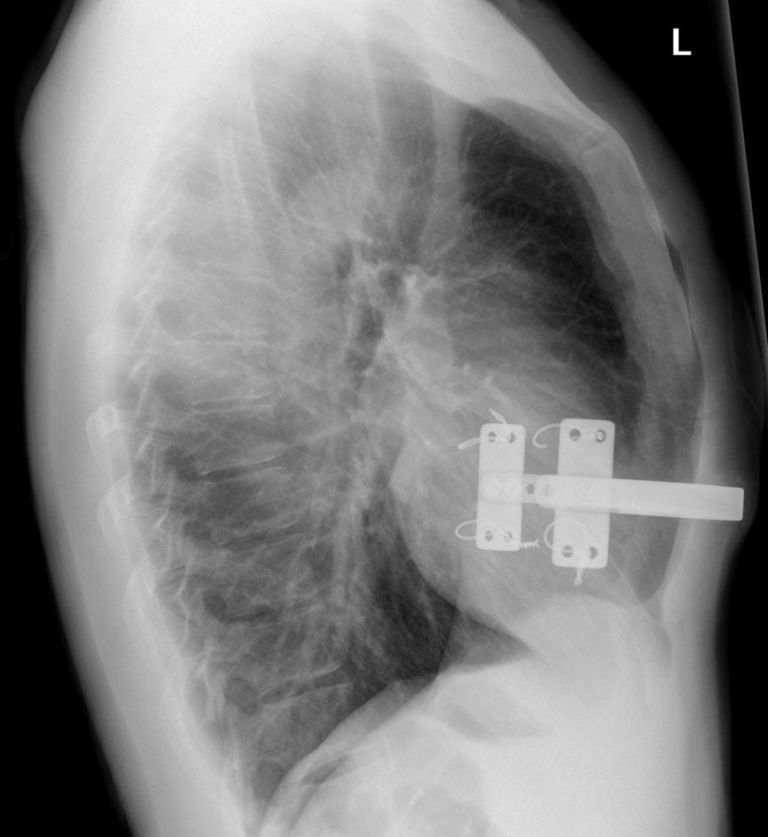

The answer to the last spotter is here. PECTUS EXCAVATUM also known as How Much Is Pigeon Chest Surgery  Pectus carinatum is a condition in which your sternum (breastbone) sticks out more than usual. Pectus carinatum, also known as pigeon chest, is when the cartilage grows up and out, which causes the sternum, or breastbone, to protrude. Although some cases will require surgery, most children with pc will need a chest orthosis, also known as a brace, to help. How Much Is Pigeon Chest Surgery.